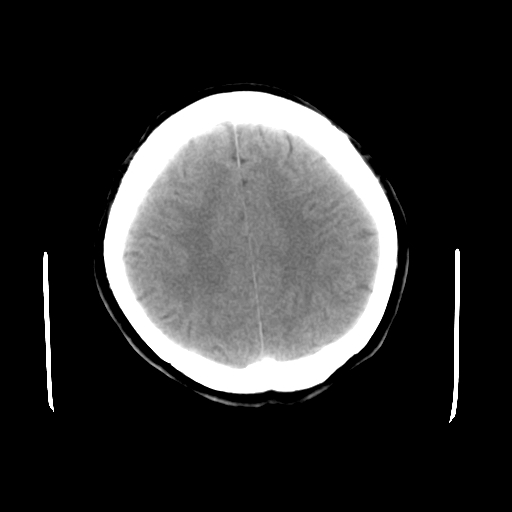

标题: CT23995:女,42岁,前额部外伤1小时,伤后头痛。 [打印本页]

女,42岁,前额部外伤1小时,伤后头痛。

头颅ct平扫未见异常

未见明显异常!

颅脑ct平扫未见异常,必要时复查

未见明显外伤性改变。